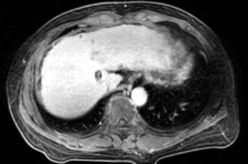

Ø 术前影像学检查

肝 S2 段及肝 S4 段见类圆形 T1WI 低、T2WI-SPAIR/DWI/ADC 高信号,较大者长径

约 10mm,界清。

静脉期